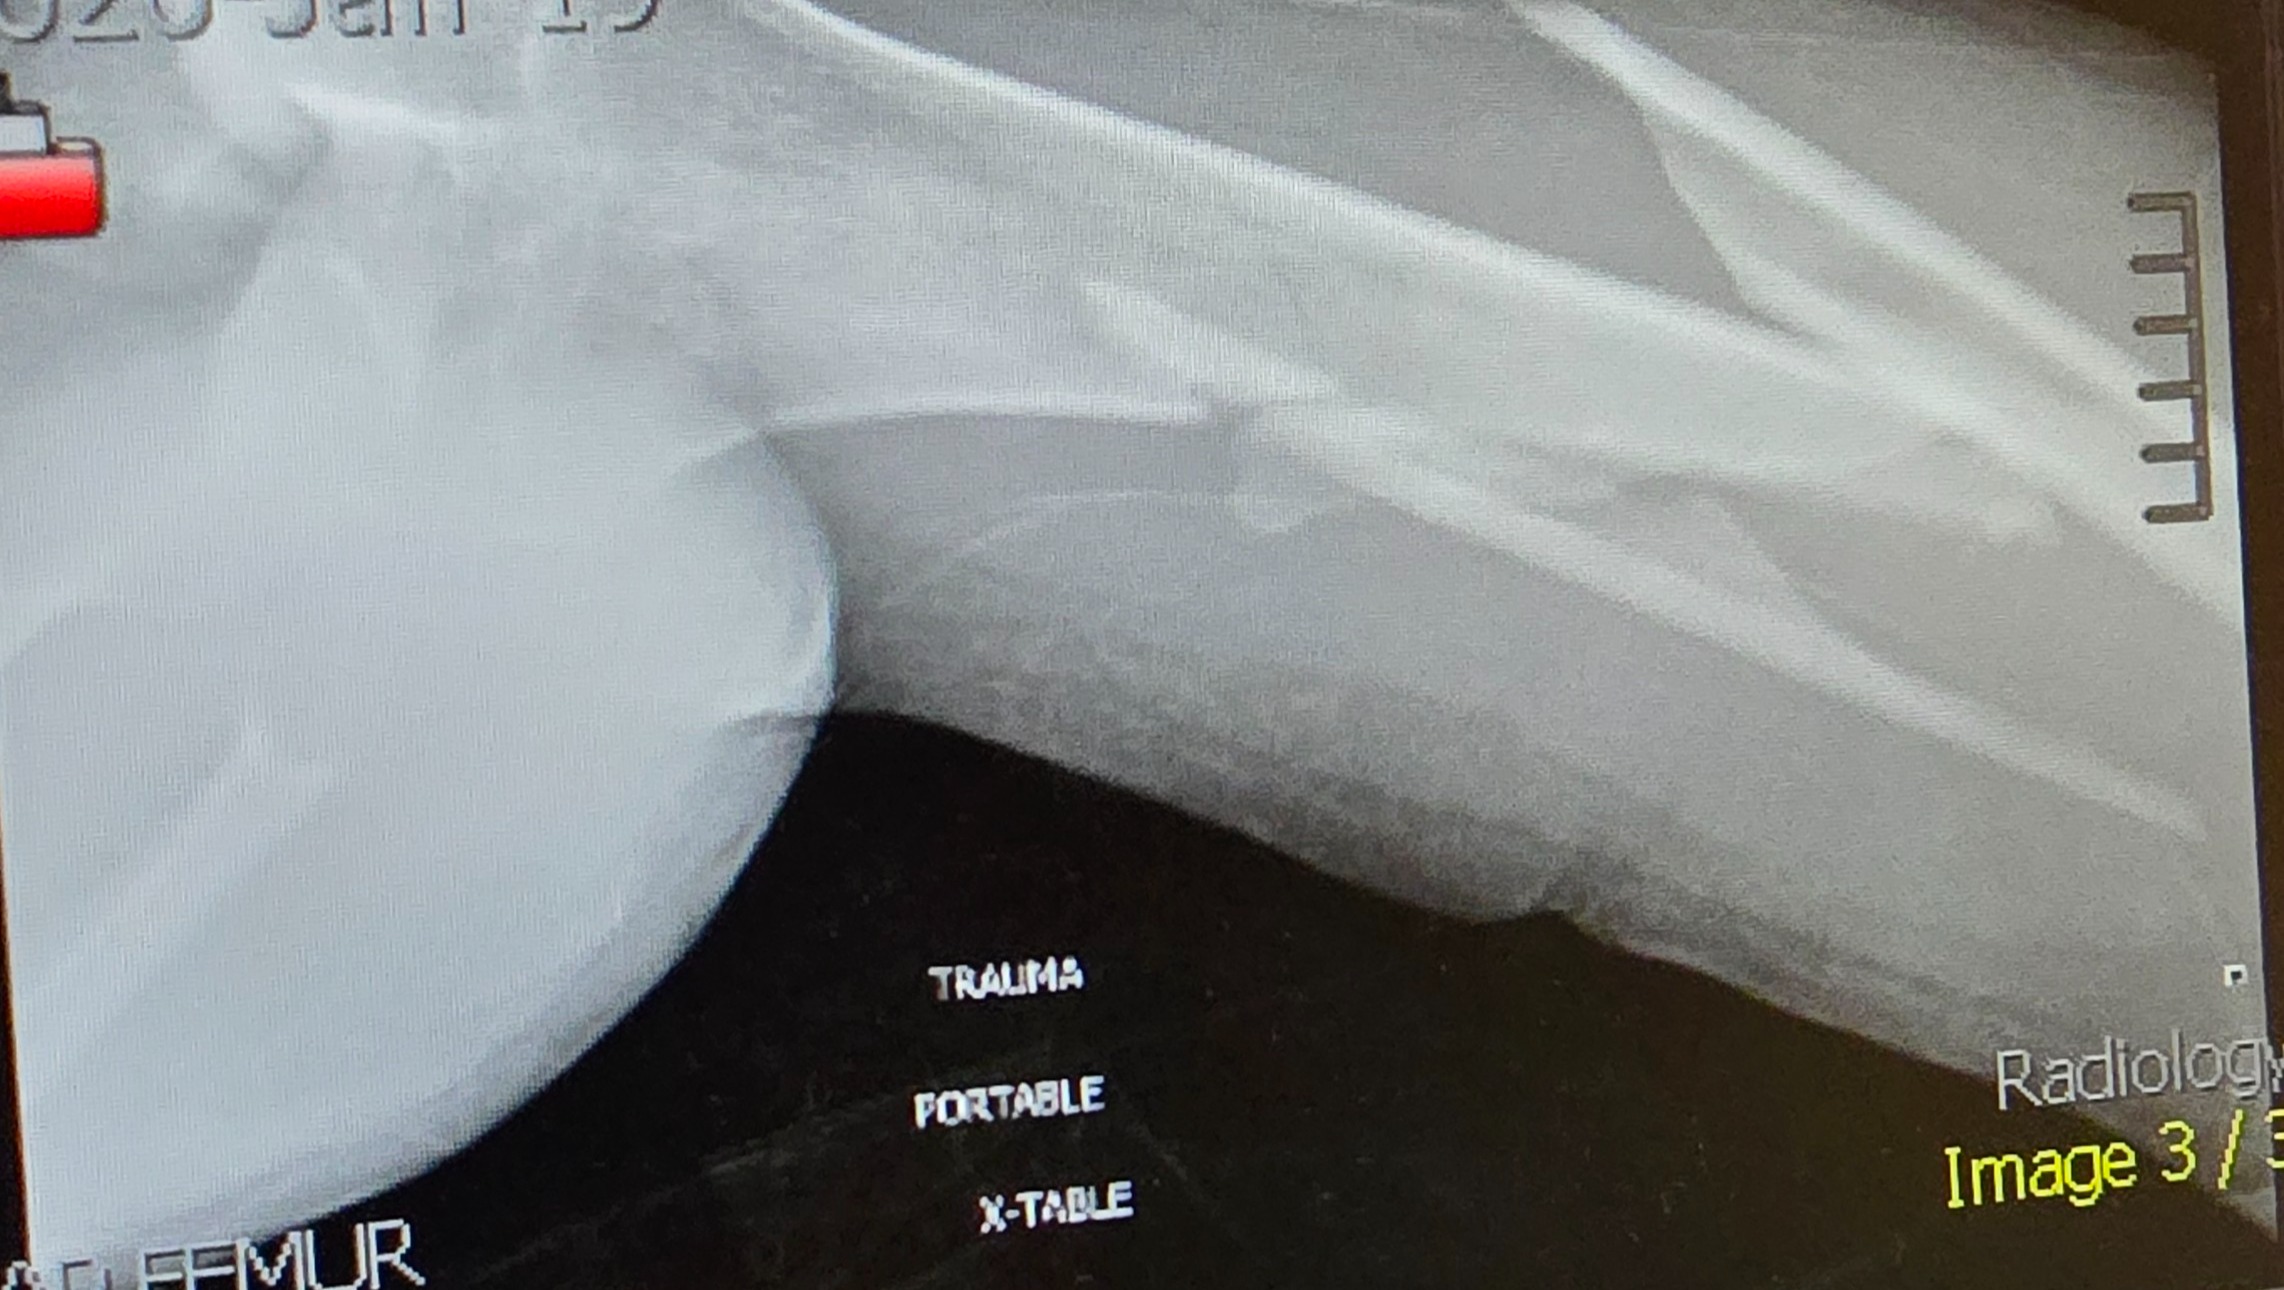

Even though he was wearing his seatbelt, the entire impact hit his left side. His left arm was shattered into multiple pieces, causing severe nerve damage. His left femur was broken into three pieces. He also struck his head against the window.

He was rushed to the hospital, where he spent a long night in unbearable pain before undergoing nearly eight hours of emergency surgery the next morning. Surgeons worked tirelessly to reconstruct his arm and leg. Today, Cole lives with metal rods and screws permanently placed in both his arm and leg.